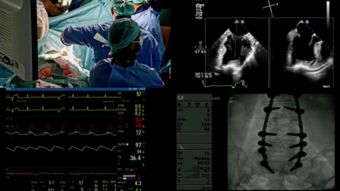

Live Case Tavi Device Selection For Severe Aortic Stenosis

Heart Center Hirslanden Zurich Heart Valve Disease Tricuspid Regurgitation Tricuspid Valve Youtube

Heart Center Hirslanden Zurich Heart Clinic Zurich Cardiology Zurich Heart Surgery